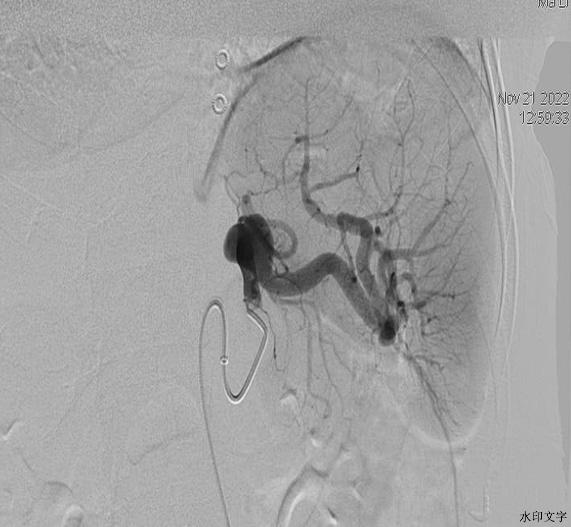

41岁的马女士,因体检发现脾动脉瘤入住我院普外科。普外科邀请介入科赵蔚主任会诊,结合患者脾动脉瘤重建图像,赵主任建议行DSA引导下动脉瘤内微弹簧圈栓塞术。经过详细体格检查、排除手术禁忌症,次日,赵主任和主治医师代福联合为该患者行局麻下腹腔动脉造影检查,造影示动脉瘤位于脾动脉近段,以6F超长血管鞘引入5F肝动脉导管于动脉瘤体近端,以2.7微导管于动脉瘤腔内反复盘旋后释放1枚带纤毛微弹簧圈(14mmx50mm),造影复查再次填补1枚(6x10mm)普通微弹簧圈后动脉瘤体内未见明显血流,脾动脉主干血流未见受损,栓塞效果满意。术后患者生命体征平稳,现已康复出院。